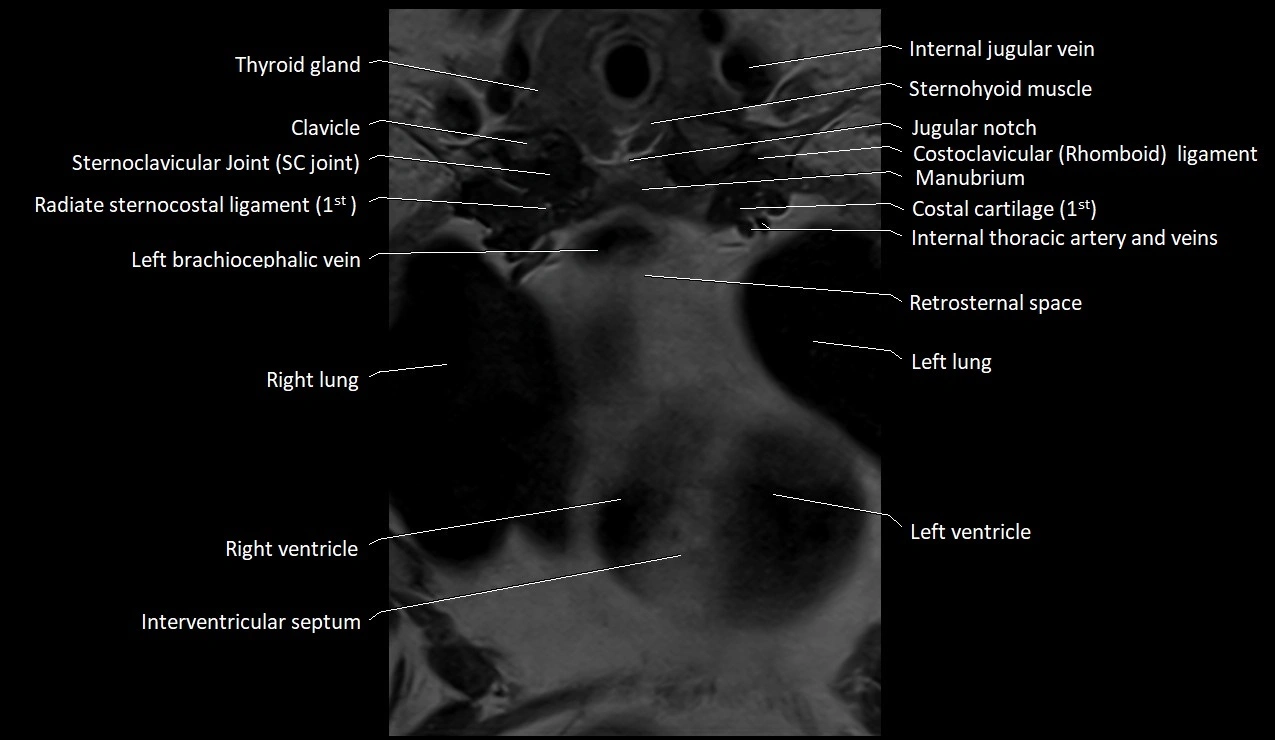

MRI images

image